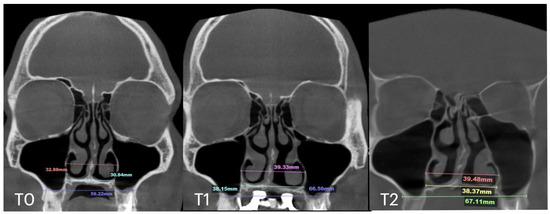

2.4. Case A: Blind Midpalatal Piezocorticotomy with MARPE Expansion

| Case A | 30.84 | 38.15 | 38.37 | 59.22 | 66.37 | 67.11 | 32.8 | 39.33 | 39.48 | 28.01 | 32.88 | 33.38 | 10.5 |